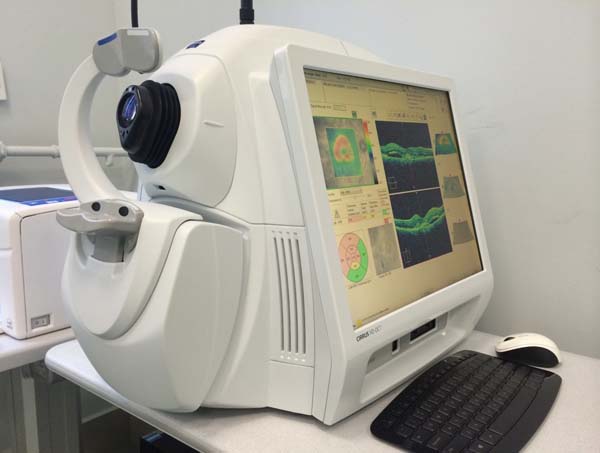

Диагностика зрения: Когерентная томография сетчатки

Раздел: Фотоальбом решений